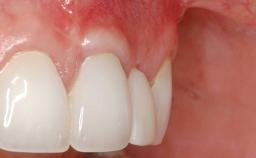

Implant Placement in the Esthetic Zone and Coverage of Multiple Gingival Recessions

This case illustrates use of a modified ‘tunnel’ technique, which has been shown to be highly effective in root coverage procedures. The tunnel technique is used to achieve soft-tissue augmentation across the anterior area, including the planned implant site, using collagen matrix as grafting material. The patient is a 47-year-old woman with high esthetic expectations. Her main concern was the appearance of the anterior teeth and their “elongation”.